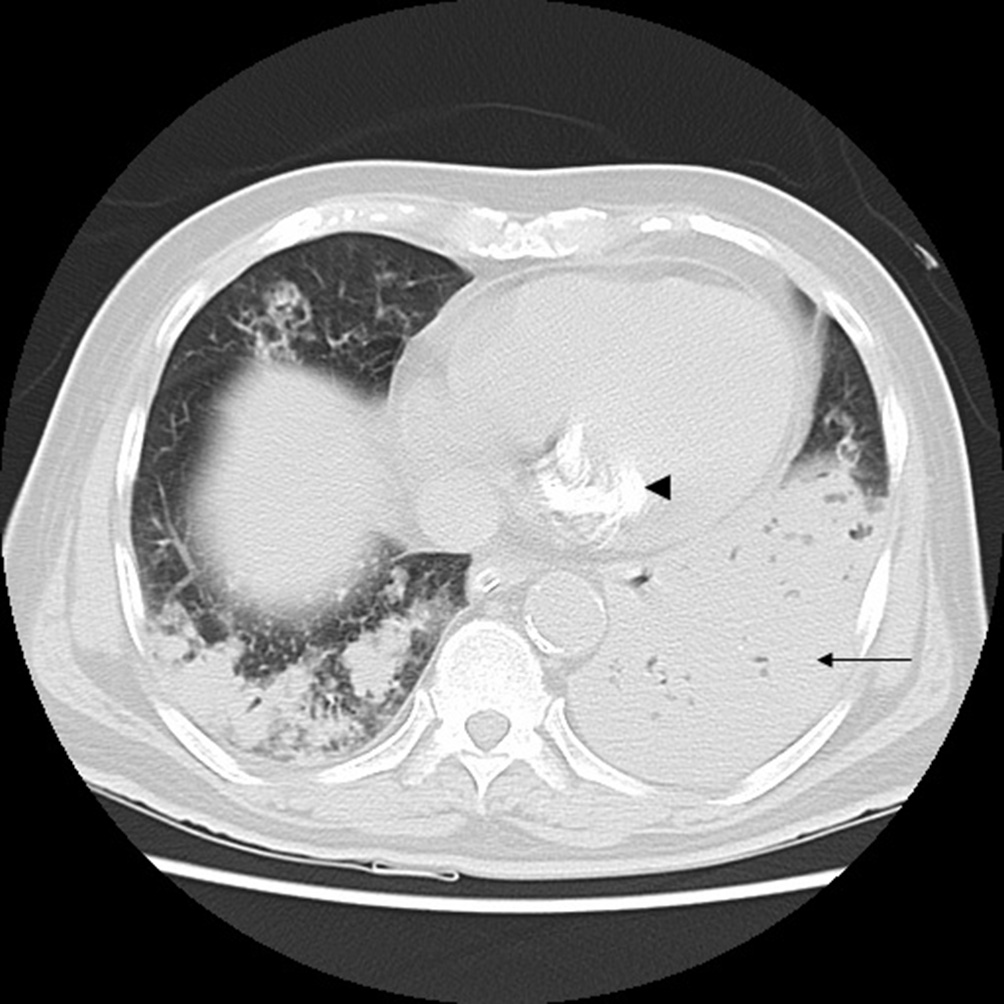

Fig. 4. Incidental mitral annular calcification (arrowhead) is seen. Thin arrow indicates consolidation. Fig. 5. CT transverse section (lung window) shows bilateral nodular lesions in bilateral upper lobes with central cavitation (arrows) in a few lesions on left.

He was initiated on ceftriaxone, azithromycin and non invasive ventilation for mild ARDS(Acute Respiratory Distress Syndrome). On day 4 of hospital stay, his breathing mechanics worsened and he was initiated on mechanical ventilation in view of worsening ARDS and pneumonia. Endotracheal aspirate culture initially revealed Staphylococcus aureus which was subsequently turned out to be contaminant. To rule out pulmonary tuberculosis two samples were sent for AFB smear (Acid Fast Bacillus)examination and were found to be negative. Mycobacterial culture was sent. CT thorax on day 8 showed bilateral extensive areas of consolidation (Figs. 2e4) with multiple small cavitating nodules (Fig. 5). Special stain for Nocardia was done on the broncho-alveolar lavage e Kinyoun stain was done which revealed weakly acid fast branching bacilli (Fig. 6). Culture of the BAL was done on 5% Sheep blood agar and chocolate agar which revealed chalky white colonies after 3 days of incubation. These were identified Nocardia sps on staining morphology on Grams stain and Kinyoun stain. He was initiated on trimethoprim and sulphamethoxazole. Subsequently he had VAP (Ventilator Associated Pneumonia) with gram negative bacteria, and was treated as per sensitivity. Tracheostomy was performed and weaned off ventilator.